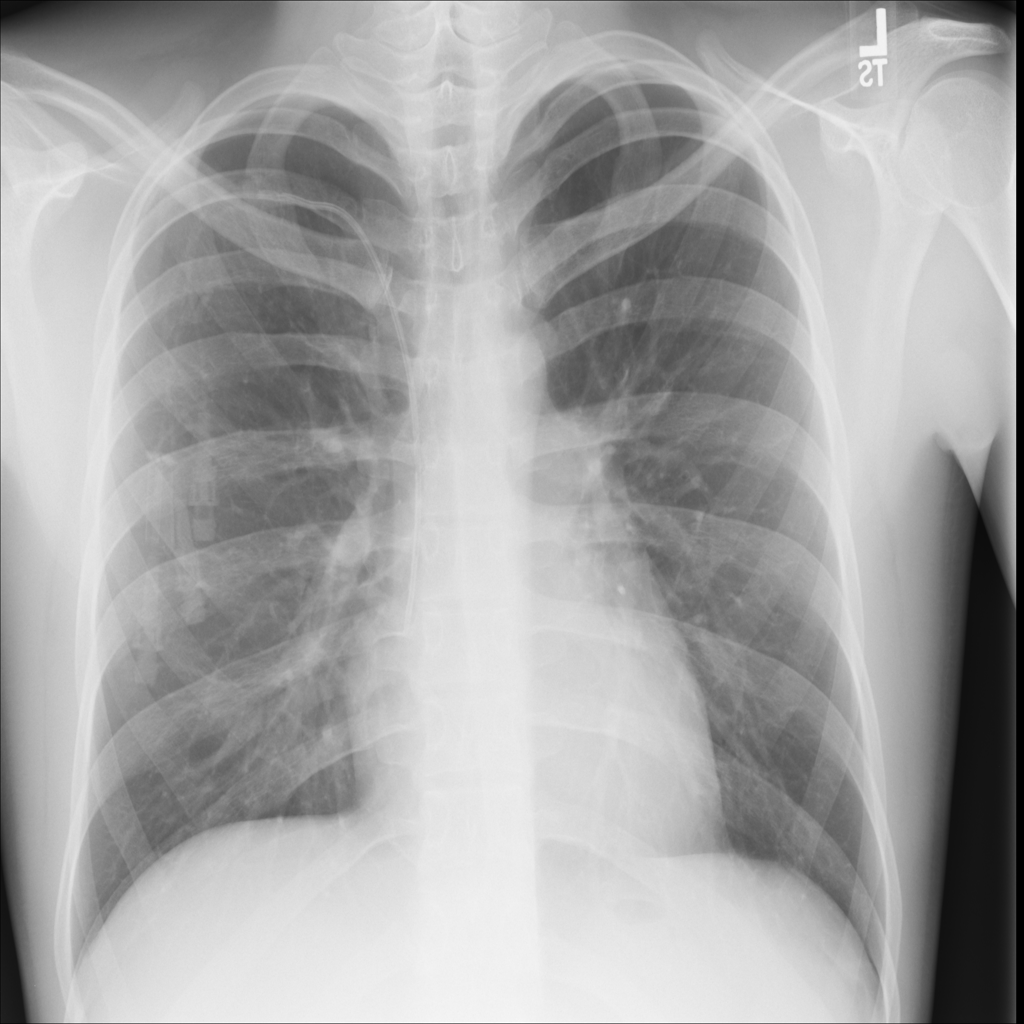

PAT-C0E5 · IMG-015Pneumonia

PAT-C0E5 · IMG-015

AP